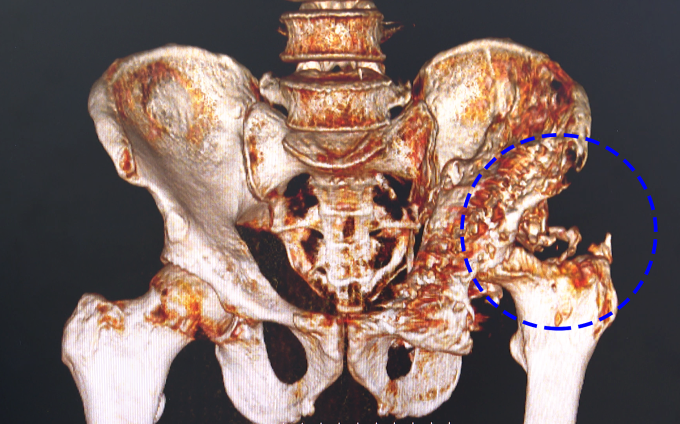

Kết quả chụp phim CT tại Bệnh viện Đa khoa Tâm Anh Hà Nội cho thấy ông bị tiêu xương hoàn toàn chỏm đùi trái, lan rộng quanh ổ cối, gợi ý vẫn còn ổ nhiễm trùng tiềm ẩn trong khớp háng. ThS.BS Nguyễn Quang Tôn Quyền, Phó khoa Chấn thương Chỉnh hình, khuyên ông Trúc nên ngừng toàn bộ kháng sinh trong 2-3 tuần để nuôi cấy dịch khớp, kiểm tra chính xác nguyên nhân gây nhiễm khuẩn, tái khám ngay khi có triệu chứng tái nhiễm trùng. Ba tuần sau, khớp háng bệnh nhân sưng nề, đau dữ dội, da đỏ tấy. Xét nghiệm chọc dịch khớp háng, nuôi cấy vi khuẩn dương tính với tụ cầu vàng (Staphylococcus aureus) kháng kháng sinh rất mạnh.

Phim chụp CT ổ nhiễm trùng gây tiêu xương nặng của ông Trúc. Ảnh: Bệnh viện Đa khoa Tâm Anh